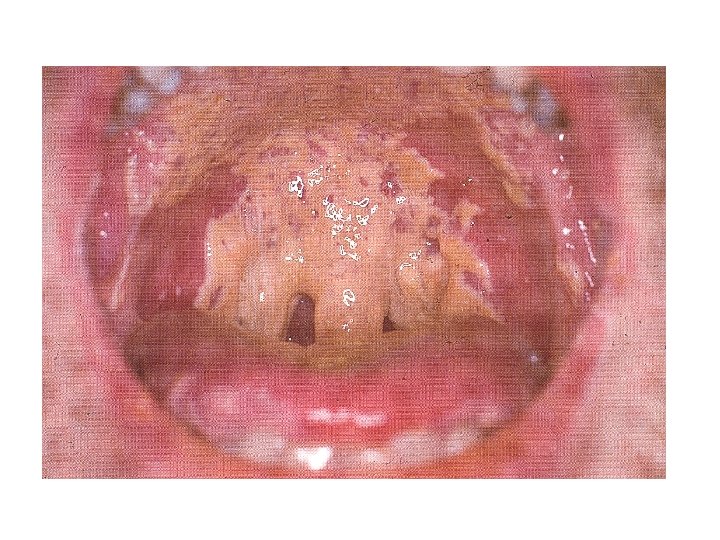

Case Four • Sara, a 32 year-old accountant, presented with retrosternal pain associated with swallowing of both solid and liquid foods of two weeks duration • She also reports generalized body weakness and weight loss • One month back she developed whitish oral lesions, treated with topical antifungals

Discussion • What would you include in your initial differential diagnosis? • What would you expect to find on physical examination?

Physical Examination • She was chronically sick looking • Vital signs were all in normal range • Small, unremarkable posterior cervical lymph nodes • Extensive oral candidiasis • Chest clear • No other pertinent findings

Discussion • How does this additional information affect your differential diagnosis? • How do you investigate this patient?

Differential Diagnosis • • Esophageal candidiasis CMV esophagitis HSV esophagitis Kaposi's sarcoma or lymphoma Idiopathic ulcers (aphthous ulcers) Gastroesophageal reflux disease Combination of 2 or more

Diagnostic Interventions • KOH from oral lesion • Barium swallow • Endoscopy and tissue biopsy – – – Tissue staining for CMV Fluorescent antibody tests Antigen detection tests (CMV & HSV) Polymerase chain reaction (PCR) Viral culture • None of these are necessary if typical presentation and response to empiric treatment using fluconazole, 100 -200 mg/d

Therapy • Esophageal candidiasis would be the most likely diagnosis in this patient – Fluconazole 200 mg/day PO (up to 400 mg/day) for 14 -21 days – Alternative treatments • Ketoconazole 200 -400 mg PO qd for 14 -21 days • Itraconazole 200 mg PO qd for 14 -21 days

Genital and Oral Lesions